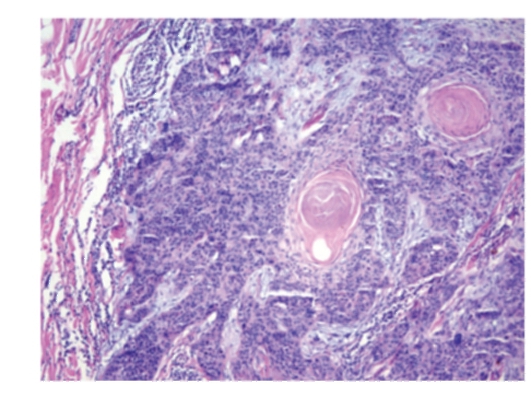

Исследование: микропрепарат молочной железы в медицине

Раздел: Снимки-откровения